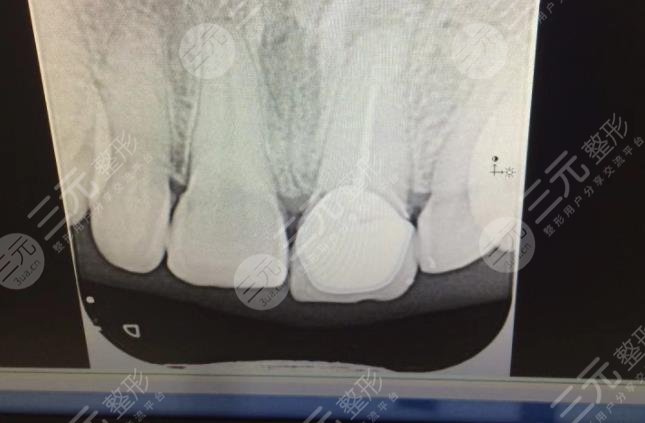

于自己的牙齿一定要保护好,牙齿咬住之后就没有办法再长出来了,年纪轻轻的如果就出现了牙齿脱落较为的尴尬,戴假牙不方便,只能做牙齿种植。像我就是一个典型的案例,之前一次意外事故导致了门牙的脱落,像我这种较为注意形象的女生来讲,出现门牙的脱落可以是灾难性的损坏。赶紧到医院咨询了一下,还好医生说现在可以做牙齿种植。

在整个手术的过程当中采用的是局麻。意识较为的清楚,能够感觉到医生的操作,但是却没有觉得疼。手术的速度还是比较快的。牙齿种植的过程其实是比较复杂的,虽然说具体的流程不知道,但是整个持续了半年左右的时间才基本完成牙齿种植。

至于牙齿种植之后的果,确实可以推荐,在做牙齿种植之后,新植入的牙齿较为的坚固,丝毫不逊色于自己的牙。除了坚固之外,关键还是美观。这才是较重要的,通过牙齿种植让我又像原来一样了。